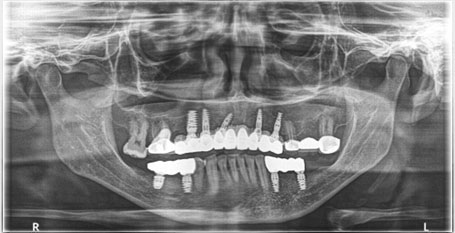

OPG after implant treatment.

This is the case where we have placed 5 implants in the upper jaw and 2 implants in the lower right back side and 2 implants in the lower left back side of the jaw.

OPG

All on 4 implant placements in lower jaw

In the below case, lower teeth were not sound and not savable too. so, we decided to remove lower teeth and give patients fixed teeth with the help of dental implants. upper teeth were strong enough, so we decided to save and did Philips zoom teeth whitening to get a better look of the patient.